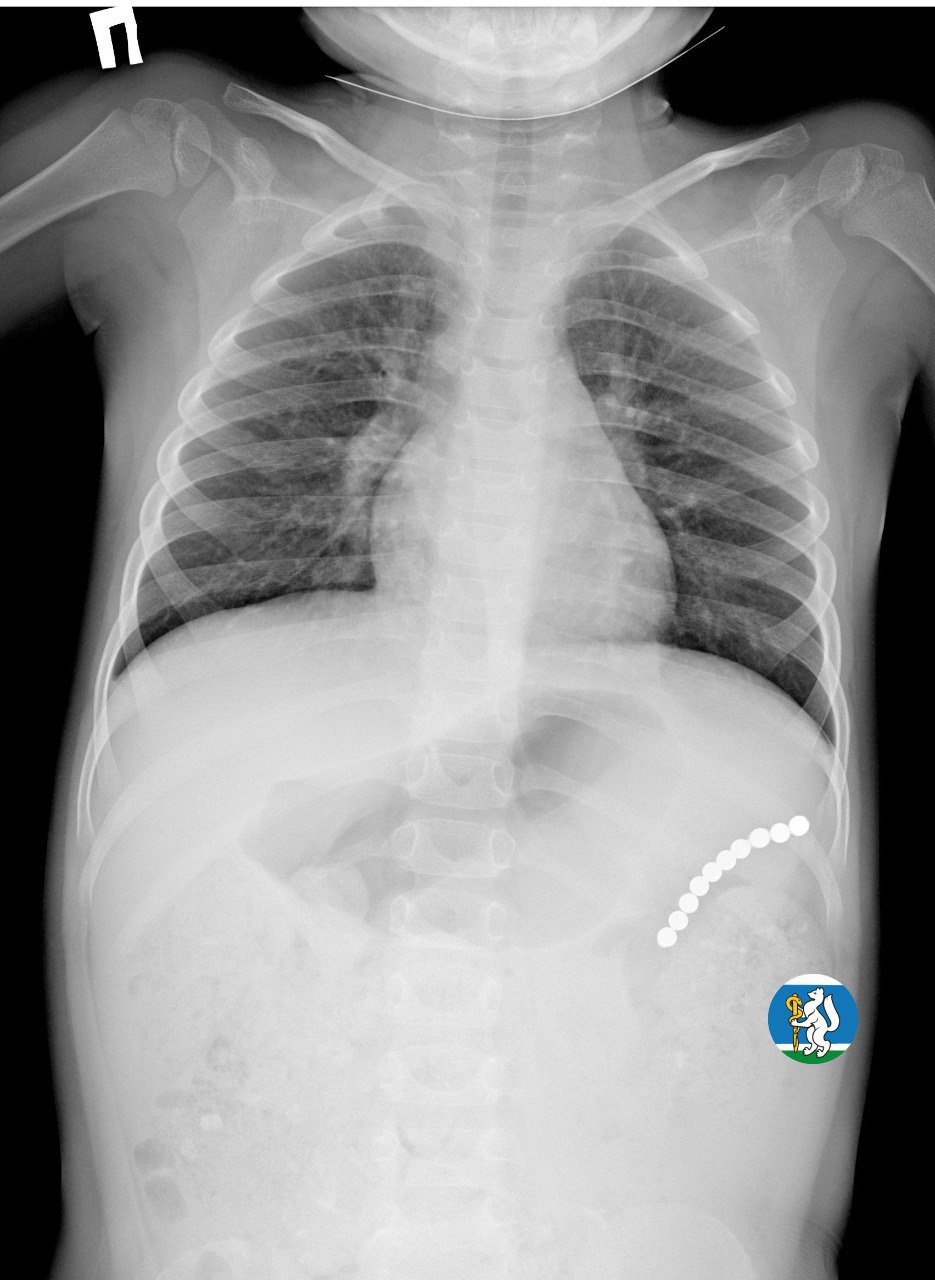

«Малышка почувствовала недомогание, и семья пришла на консультацию к участковому педиатру. Для исключения пневмонии был выполнен рентген органов грудной клетки. Благодаря этому на снимке в проекции желудка диагносты обнаружили чрезвычайно опасный предмет — цепочку магнитных шариков, которые травмировали стенки органов пищеварительной системы и могли стать причиной перитонита. В связи с угрозой жизни Ульяну оперативно госпитализировали в Детскую городскую клиническую больницу №9, где ей оказали всю необходимую помощь», — рассказала заместитель губернатора - министр здравоохранения Татьяна Савинова.